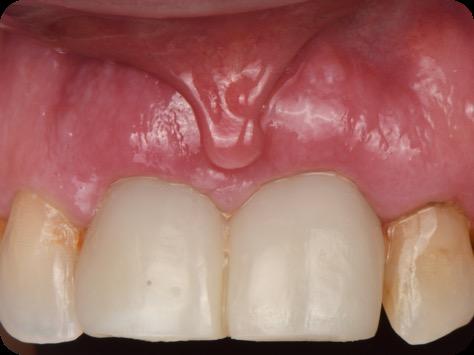

BioHorizons has introduced a new implant system that combines the advanced thread design of the Tapered Pro with the precision and stability of the Conelog conical connection. This integration delivers enhanced surgical handling, improved primary stability, and long-term biological benefits, supporting better patient outcomes in both aesthetic and functional zones.

This case was performed by Dr Homa Zadeh, DDS, PhD, a respected leader in periodontology and implant dentistry. Dr Zadeh’s approach emphasizes biologically driven protocols and evidence-based techniques, making this case a strong example of clinical excellence using the Tapered Pro Conical system. It involves the replacement of two front anterior teeth after they fractured off and the full restoration process.

Fig 16. Patient’s smile after implantation and previsualization